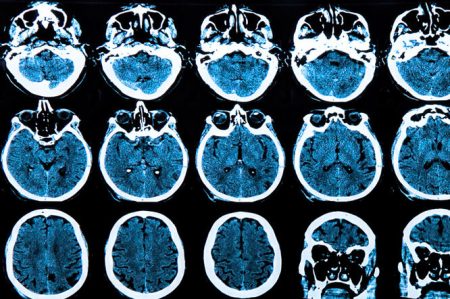

Huntingtonova bolest je nasljedni neurodegenerativni poremećaj koji progresivno utiče na motorne funkcije, kognitivne sposobnosti i emocionalno stanje oboljelih. Uprkos decenijama…